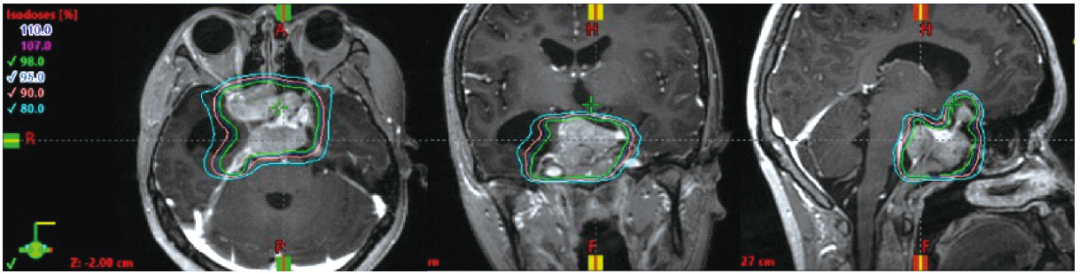

对于颅内肿瘤,调强放射治疗技术相较于三维适形放射治疗或常规放射治疗技术,可显著降低正常脑组织的受照剂量[8-9]。同时,由于调强放射治疗剂量分布的高适形性,采用分次治疗的剂量分割方式(图2),可保证肿瘤周边的视交叉、视神经及脑干在放射耐受剂量之内。

图2 1例垂体巨大腺瘤患者调强放射治疗治疗计划剂量分布

绿色为98%等剂量曲线,与肿瘤形状高度适形,高剂量区避让了后方脑干及两侧颞叶